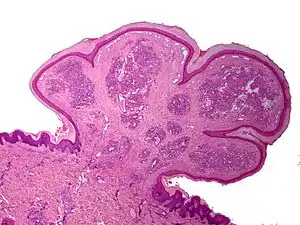

One study has suggested a correlation between pyogenic granulomas and Bartonella seropositivity.[8] However, this association has been questioned by others.[9] The microscopic appearance of a pyogenic granuloma consists of highly vascular granulation tissue. Inflammation is present. The lesion may have a fibrous character if it is older, and the surface may have ulcerations. Pyogenic granulomas rarely occur in the conjunctiva, cornea or connective tissue of the eye following minor local trauma. Grossly these mass lesions resemble those occurring at more common sites. The relationship of these lesions to lobular capillary hemangiomas of skin and oropharyngeal mucosa commonly referred to as pyogenic granuloma is uncertain.

Histopathological examination shows multiple capillaries (due to the vascular nature of the tumour), neutrophils (pyogenic) and necrotic tissue.